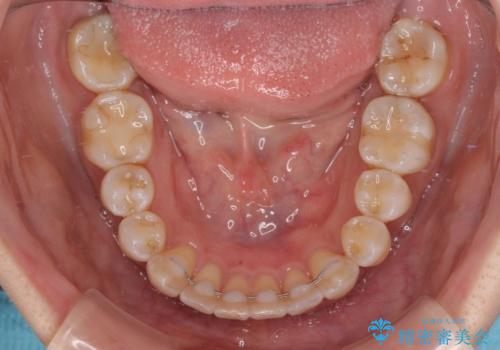

気になる八重歯 ワイヤー装置での非抜歯矯正

- 上顎の八重歯と全体的なデコボコを気にして来院された患者様です。

口元の突出感はなかったため非抜歯矯正での対応となりますが、八重歯を改善する際に上顎前歯が前突する可能性があったため、上顎臼歯部にアンカースクリューを使用して、歯列が前方に転位しないようにすることとしました。

また舌のトレーニングを行うことで、上顎前歯の突出予防や上下前歯に隙間ができなくなるようにしました。

ワイヤー矯正でもインビザラインでも対応可能でしたが、上顎歯列が前方位であるときには、ワイヤー矯正の方がより良い仕上がりとなる可能性が高いため、ワイヤー矯正をおすすめいたしました。